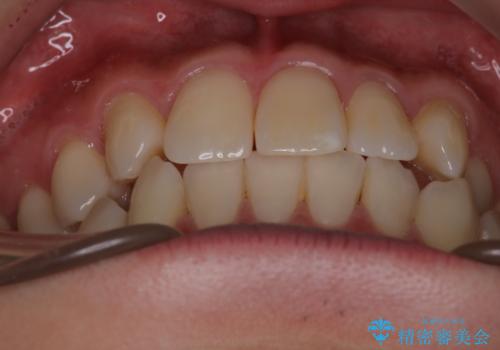

- 右上2番が欠損しており、歯並びをバランスよくしたいということで来院されました。

ワイヤー装置とマウスピースで悩まれていましたが、マウスピースで治療可能と判断致しましたのでマウスピースにて治療しました。

IPR、歯列弓拡大、ゴム掛けを行い歯並びを整える治療計画を立てました。

右上2番が欠損しているため、見た目と噛み合わせの両方のバランスを整えるために経過を追いながら必要な部位にゴム掛けをしました。

最終的に、見た目も噛み合わせも患者様に満足いただけました。